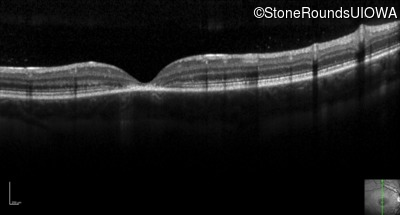

Optical Coherence Tomography - Right - 20/80 -2 sc

Exemplar / OCT Stack

Optical Coherence Tomography - Left - 20/80 -2 sc